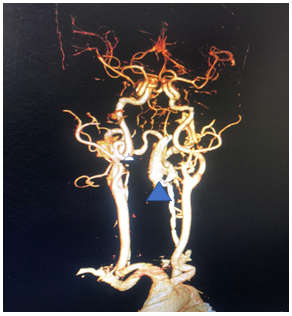

The Persistent Trigeminal artery maintained good flow in the vertebral artery allowing for good filling of the basilar artery and its vital branches (Figure 8). The Persistent Trigeminal Artery connect the anterior circulation directly to the basilar artery. Hence, damage to 1 or more vertebral arteries will not reduce blood flow to the brainstem. Hence these patents have a high tolerance for vertebral artery manipulation and even thrombosis. The procedure was stopped, and the patient was extubated. Post op he was deficet free, alert conscious and content. The femoral sheath was removed the next day, and the patient was mobilized and discharged after 2 days. He has review in OPD after 3 months and repeat angiographic investigations have showed no filling in the EDAVF ever since.

Figure 8 Persistent Trigeminal artery seen here supplying the basilar artery seen clearly in this angiographic sequence and pointed at by the arrow.

Our case was aided by a very fortuitous occurrence of the primitive Trigeminal artery which was patent allowing us the manipulate the left vertebral artery without fear of consequences which may lead to hypoperfusion of the brainstem (spasm, dissection, rupture, or thrombosis). Post procedure flow was excellent allowing adequate perfusion of the brainstem throughout the procedure.